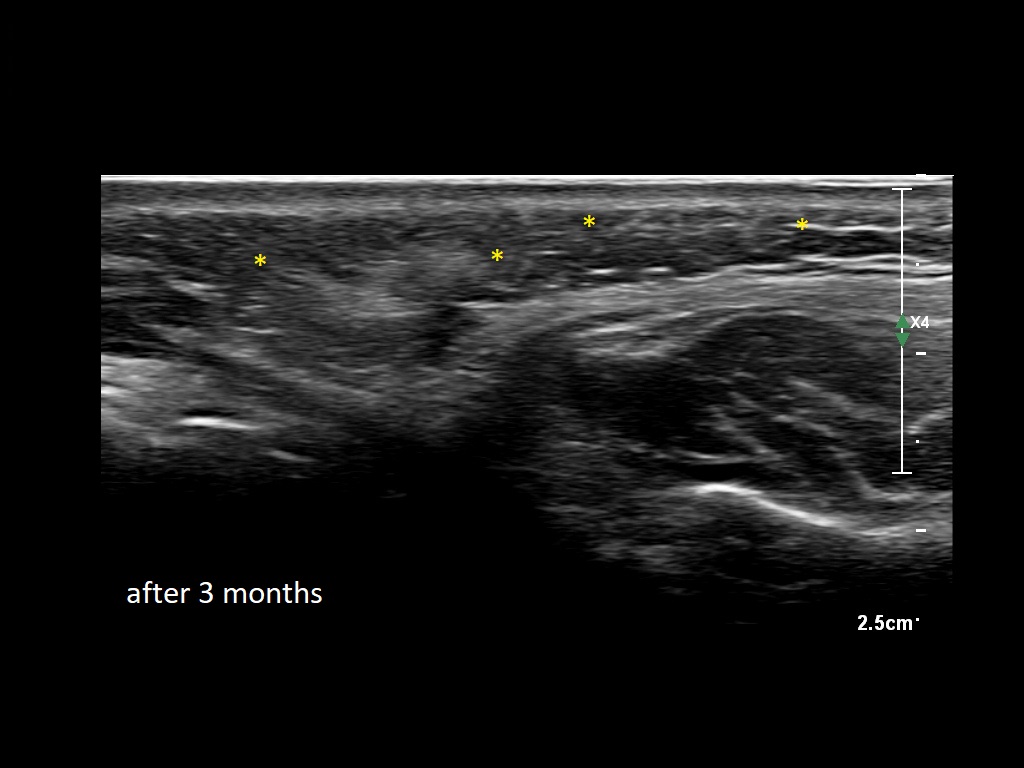

Draw in the second image below where the fillers are located. To check if your answer is correct, swipe the first image to the right.